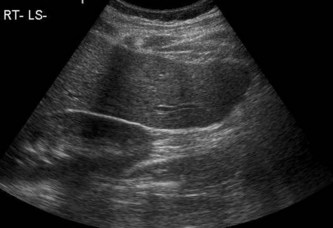

Как выглядит доля Риделя на УЗИ печени